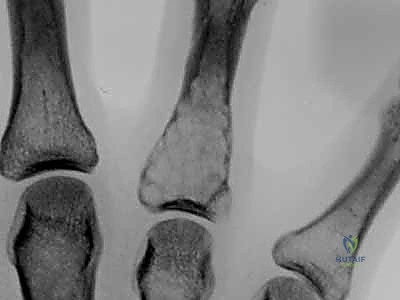

1. عظام اليد والأصابع (Phalanges & Metacarpals): عظام صغيرة جدًا وأنبوبية. وجود ورم هنا (مثل الورم الغضروفي) يؤدي إلى انتفاخ العظمة وتشويه شكل الإصبع، مما يعيق الحركة.

* الموقع المفضل: عظام المشط (Metacarpals) وسلاميات الأصابع (Phalanges).

* الأعراض: غالبًا ما يكون صامتًا ولا يسبب ألمًا (يُكتشف بالصدفة عند إجراء أشعة لسبب آخر). ولكن عندما ينمو، يسبب انتفاخًا غير مؤلم في الإصبع. الألم عادةً ما يكون مؤشرًا على حدوث كسر مرضي دقيق داخل العظمة الضعيفة.

| شكل الأشعة السينية | تكلسات منقطة (Popcorn calcification) | فقاعات الصابون (Soap bubble appearance) | تجويف شفاف مركزي |